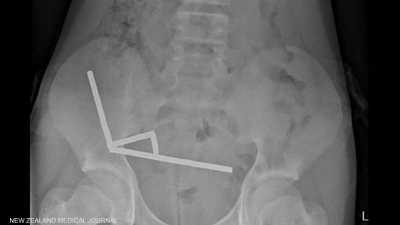

صبي يبتلع 100 مغناطيس اشتراها من "تيمو".. والشركة تعلق